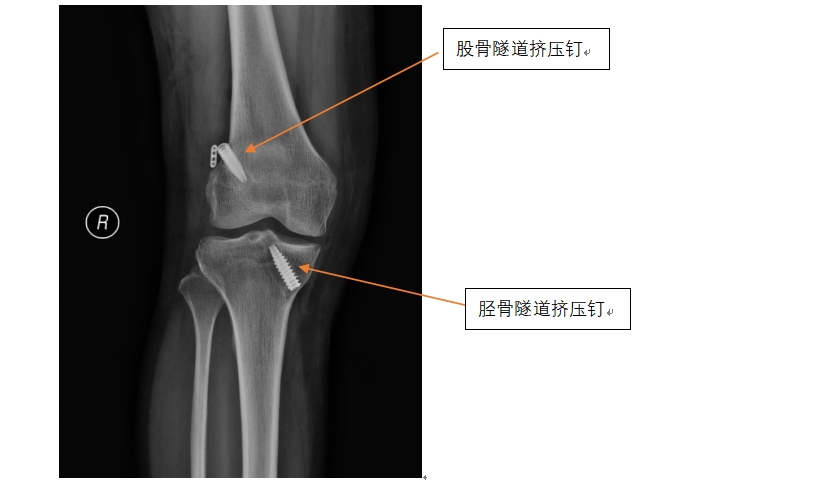

前叉韧带翻修手术难度要明显大于初次手术,术前黄遂柱博士团队就对第一次手术时制作的骨隧道进行了认真评估,最困难的情况就是第一次手术的骨隧道位置不是特别理想,但又没有在完全错误的位置上,最终黄博士团队还是克服了各种困难,成功地实施了人工韧带翻修手术。术后配合我院特有的中医药技术以及护理团队的密切配合,患者恢复非常顺利,术后一周患者出院时已经能够比较自由地脱拐行走,患者对治疗结果非常满意,术前的焦虑情绪也一扫而光。